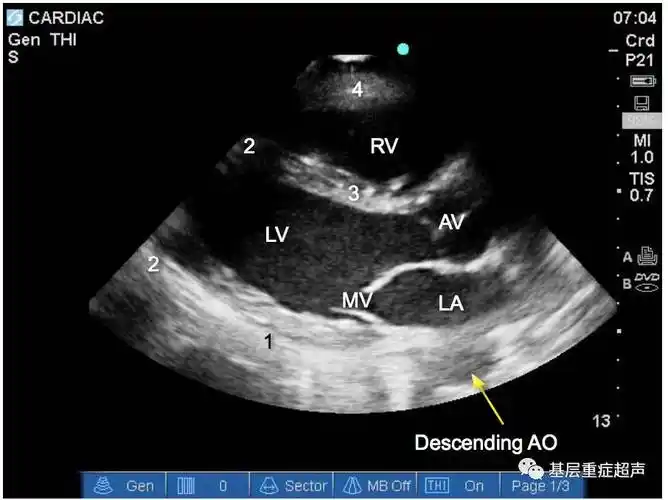

超声心动图切面介绍胸骨旁长轴胸骨旁短轴心尖切面剑突下切面